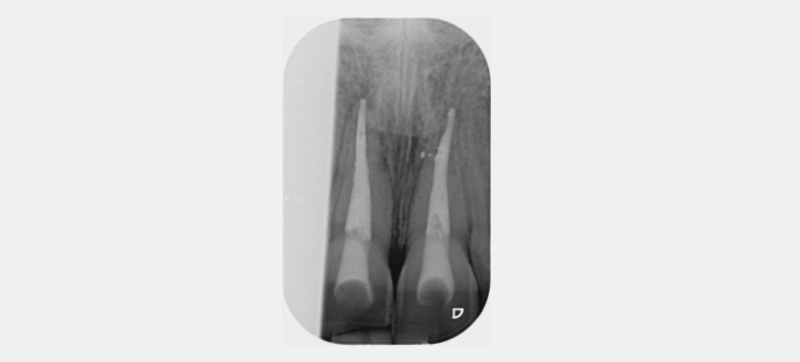

- The RMGIC coronal barrier seal is placed. The position is verified with a periapical radiograph. This is important for both clinical and medico-legal reasons.

Figure 23 shows the endodontic treatment, the coronal barrier seal, and the final palatal composite restoration.